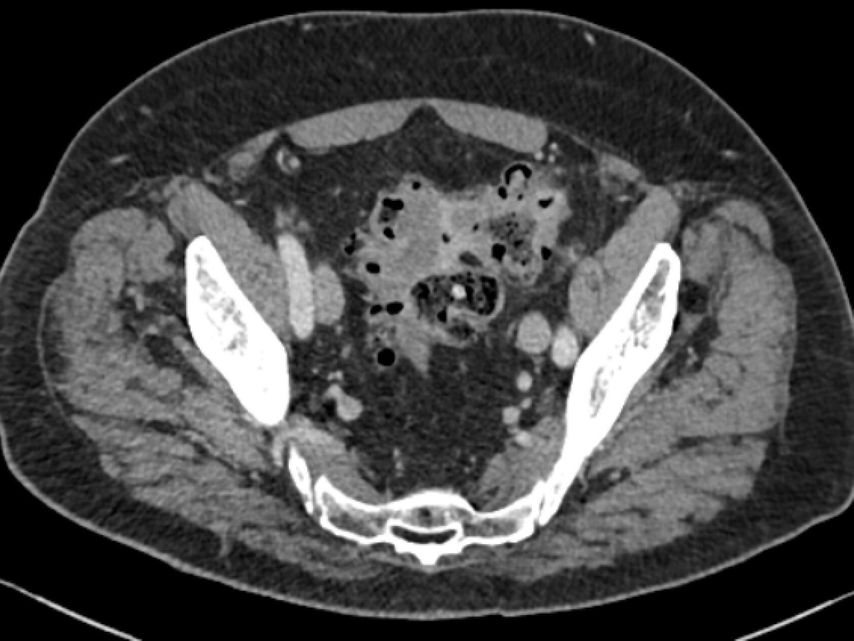

maladie diverticulaire chronique (maladie diverticulaire symptomatique récidivante ou persistante; type 3a–c) (Fig.4).

Diverticulite chronique récidivante

La diverticulite chronique récidivante de type 3b est pertinente dans la pratique clinique quotidienne. Elle se caractérise par des inflammations récurrentes et intermittentes des diverticules. Contrairement à ce que l’on pensait auparavant, les évolutions des poussées récurrentes ne sont pas plus intenses ou plus à risque. Le risque de perforation est considéré comme le plus élevé lors de la première poussée et diminue ensuite. Les intervalles entre les poussées inflammatoires ne peuvent pas être prédits.5 L’indication d’une opération et d’un nettoyage du foyer ne dépend plus du nombre de poussées inflammatoires antérieures. Les éléments essentiels pour la décision sont plutôt la dégradation de la qualité de vie due aux poussées inflammatoires ainsi que la détermination du rapport bénéfice-risque d’une opération. Une opération élective par intervalles se basant uniquement sur le nombre de poussées inflammatoires antérieures n’est pas considérée comme justifiée.

Pour la classification de la diverticulite sigmoïdienne, la «Classification of Diverticular Disease» (CDD) s’est imposée (Tab. 1). Celle-ci a pour but de recueillir les différentes évolutions indépendamment d’une opération ainsi que de stratifier les différents pronostics et options thérapeutiques lors du premier diagnostic ou en cas de récidive. Une distinction est faite entre les formes suivantes: